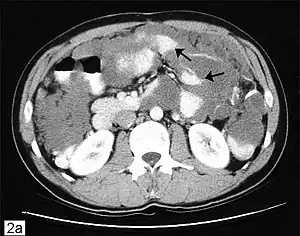

CT scanning is preferred to assess the extent of the tumor in the abdominopelvic cavity, though magnetic resonance imaging can also be used.[28] CT scanning can also be useful for finding omental caking or differentiating fluid from solid tumor in the abdomen, especially in low malignant potential tumors. However, it may not detect smaller tumors. Sometimes, a chest x-ray is used to detect metastases in the chest or pleural effusion. Another test for metastatic disease, though it is infrequently used, is a barium enema, which can show if the rectosigmoid colon is involved in the disease. Positron emission tomography, bone scans, and paracentesis are of limited use; in fact, paracentesis can cause metastases to form at the needle insertion site and may not provide useful results.[29] However, paracentesis can be used in cases where there is no pelvic mass and ascites is still present.[29] A physician suspecting ovarian cancer may also perform mammography or an endometrial biopsy (in the case of abnormal bleeding) to assess the possibility of breast malignancies and endometrial malignancy, respectively. Vaginal ultrasonography is often the first-line imaging study performed when an adnexal mass is found. Several characteristics of an adnexal mass indicate ovarian malignancy; they usually are solid, irregular, multilocular, and/or large; and they typically have papillary features, central vessels, and/or irregular internal septations.[31] However, SCST has no definitive characteristics on radiographic study.[33]